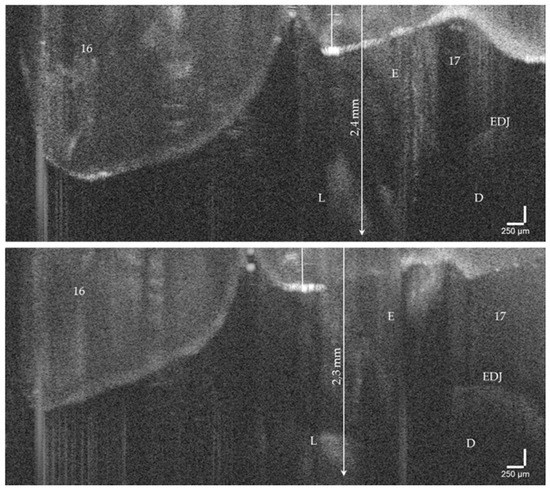

Caries, the world’s most common chronic disease, remains a major cause of invasive restorative dental treatment. To take advantage of the diagnostic potential of optical coherence tomography (OCT) in contemporary dental prevention and treatment, an intraorally applicable spectral-domain OCT probe has been developed based on an OCT hand-held scanner equipped with a rigid 90°-optics endoscope. The probe was verified in vitro. In vivo, all tooth surfaces could be imaged with the OCT probe, except the vestibular surfaces of third molars and the proximal surface sections of molars within a "blind spot" at a distance greater than 2.5 mm from the tooth surface. Proximal surfaces of 64 posterior teeth of four volunteers were assessed by intraoral OCT, visual-tactile inspection, bitewing radiography and fiber-optic transillumination. The agreement in detecting healthy and carious surfaces varied greatly between OCT and established methods (18.2–94.7%), whereby the established methods could always be supplemented by OCT. Direct and indirect composite and ceramic restorations with inherent imperfections and failures of the tooth-restoration bond were imaged and qualitatively evaluated. The intraoral OCT probe proved to be a powerful technological approach for the non-invasive imaging of healthy and carious hard tooth tissues and gingiva as well as tooth-colored restorations. Full article

Figure 1